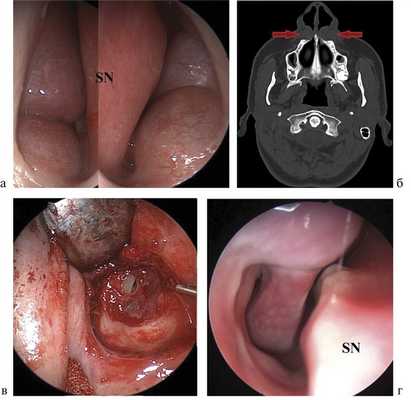

1. Пациентка А., 58 лет, обратилась в НИКИО им. Л.И. Свержевского 26.02.15 с жалобами на безболезненное шаровидное уплотнение в области крыла носа справа, деформацию лица, затруднение носового дыхания справа. Жалобы беспокоили более 15 лет, когда пациентка отметила постепенное увеличение образования мягких тканей правой щеки. Лечение не получала. При наружном осмотре в области носогубной складки и верхней переходной складки преддверия рта справа определялось плотноэластическое округлое образование, безболезненное и флюктуирующее при пальпации, диаметром 2 см (рис. 1, а). При передней риноскопии в области дна преддверия полости носа справа определялось округлое образование, прикрывающее передний край нижней носовой раковины, покрытое слизистой оболочкой с выраженным сосудистым рисунком. При МРТ в Т2-режиме визуализировалось жидкостное образование округлой формы с четкими границами, располагающееся на передней поверхности верхней челюсти и распространяющееся на дно полости носа справа диаметром около 20 мм (рис. 1, б).

Рис. 1. Больная А. а — деформация лица за счет припухлости в области носогубной складки, смещение крыла носа справа; б — МРТ, Т2-режим. Стрелкой указана носогубная киста; в — этап операции. Дефект слизистой оболочки дна полости носа; г — больная А. на 14-е сутки после операции.

На основании полученных данных была диагностирована НГК справа.

26.02.15 выполнена цистэктомия внутриротовым доступом под эндотрахеальным наркозом. Разрез слизистой оболочки полости рта производился по верхней переходной складке справа, далее киста выделялась тупым и частично острым путем. При отсепаровке стенки кисты от слизистой оболочки дна полости носа образовалась перфорация диаметром около 10 мм (рис. 1, в), в связи с чем было наложено два направляющих кетгутовых шва на слизистую оболочку дна полости носа и дефект прикрыт лоскутом из подкожно-жировой клетчатки щеки. На слизистую оболочку преддверия рта наложены узловые викриловые швы. Пациентка выписана 02.03.15. В послеоперационном периоде наблюдался выраженный отек, незначительная инфильтрация тканей и гематома в нижнечелюстной области справа (рис. 1, г). Пациентка получала физиотерапию (УВЧ № 10) в поликлинике по месту жительства. При повторном осмотре через 3 нед сохранялось только небольшое уплотнение мягких тканей в зоне операции.

2. Больная В., 32 года, обратилась в НИКИО им. Л.И. Свержевского 16.03.15 с жалобами на ощущение дискомфорта в носогубной области, наличие безболезненного шаровидного двустороннего уплотнения, более выраженного справа, головные боли, затруднение носового дыхания. Данные жалобы беспокоили около 6 мес после перенесенной ОРВИ. Амбулаторное лечение топическими интраназальными кортикостероидами — без эффекта. При бидигитальной пальпации вестибулярной борозды с двух сторон определялись образования флюктуирующего характера, шаровидной формы, мягкоэластической консистенции. Киста в мягких тканях губной борозды была больше (1,5×2 см) на левой стороне, она более выбухала в ротовую область, чем правая. Правосторонняя киста в мягких тканях была относительно меньше (1,1×1,5 см), более выбухала в носовую полость и практически полностью обтурировала общий носовой ход (рис. 2, а). По данным КТ ОНП выявлены тени кист в носогубной области с двух сторон с переходом на дно полости носа (рис. 2, б).

Рис. 2. Больная В. а — передняя риноскопия. Выстояние носогубных кист в просвет полости носа с двух сторон (SN — septum nasi); б — КТ, аксиальная проекция. Стрелками указаны носогубные кисты с двух сторон; в — эндофотография этапа операции. Дефект слизистой оболочки дна полости носа; г — эндофотография. Состояние на 14-е сутки после операции.